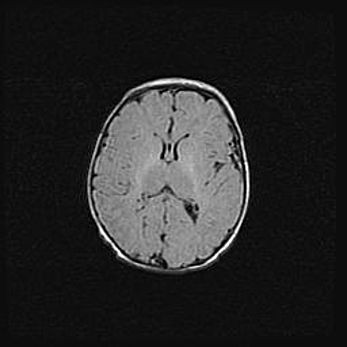

Множественные кисты обоих полушарий головного мозга, наибольшая из них в правой затылочной области. Ассиметричная атрофическая гидроцефалия.

Возраст: 7 месяцев

Вес: 5660 г

Пол: мужской

Окружность головы: 41,5 см

Срок гестации: 28-29 недель

Кисты головного мозга развиваются в результате многоочаговых некрозов вещества мозга и возникают вследствие перенесенной перинатальной инфекции, менингитов, энцефалитов, асфиксии, родовой травмы, расстройств мозгового кровообращения различного генеза. Образованию кист в веществе головного мозга плодов и новорожденных способствуют такие факторы, как высокое содержание в нем воды, недостаточная (или отсутствие) миелинизация и слабая астроглиальная реакция на повреждение.

Кисты могут сочетаться с гидроцефалией и другими поражениями головного мозга.